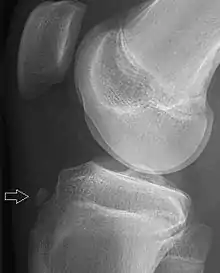

| Avulsion fracture of a fingertip bone | |